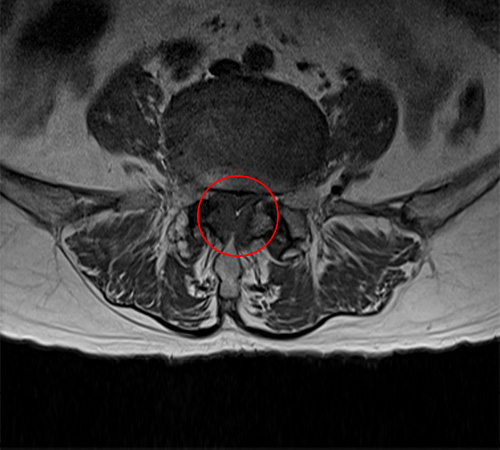

MRI 영상으로 봤을 때는 척추의 퇴행성 변화로 인해 황색인대가 부풀어오르기 시작하는 것을 협착증 초기로 봅니다. 그 다음 척추관 중앙의 공간이 30% 이상 막힌 것을 중기라고 판단하며, 척추관의 공간이 50% 이상 막혀서 심한 보행장애를 동반하는 것을 협착증 말기로 봅니다.